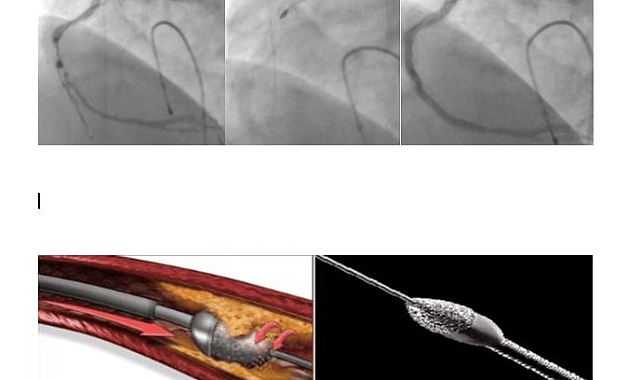

Karaman Eğitim ve Araştırma Hastanesinde İlklere İmza AtılıyorKaraman'da sağlıkta gelişim adına ilklere imza atan Karaman Eğitim ve Araştırma Hastanesinde ilk kez uygulanan ve Kardiyoloji Uzmanı olarak görev yapan Doç. Dr. Oğuz KILIÇ’ın yönetiminde nitelikli bir ameliyat daha başarı ile gerçekleştirildi.Konuyla ilgili olarak Karaman Eğitim ve Araştırma Hastanesinde Kardiyoloji Uzmanı olarak görev yapan Doç. Dr. Oğuz KILIÇ’ yaptığı açıklamasında şu ifadelere yer verdi:“Kalp damar hastalığı, koroner arter denilen, kalbi besleyen damarların tıkanması sebebiyle olmaktadır. Bu tıkanmaların en sık görülen sebebi ise ateroskleroz olarak adlandırılan damar duvarında yağlı plakların birikip zaman içerisinde damar boşluğuna doğru ilerleyip damar içinde kan akışını engellemesidir. Yağlı plaklar bazen kireçlenerek daha katı ve sert plaklar oluşturmaktadır. Bu kireçlenmiş plaklar ise bazen tıkanıklığı açmakta kullanılan balon/stent gibi malzemelerin geçişini engellemekte ve imkânsız kılmaktadır. Sonuçta balon/stent damar tıkanıklığı içerisinden geçemediği için tıkanıklık açılamamaktadır. Ek olarak, uygun olmayan malzemelerin kullanılması ile damarda yırtılma ve delinme gibi sorunlara yol açarak hastanın hayatını tehlikeye atan durumlar ortaya çıkmaktadır.Bu sert plakların açılmasında birtakım yeni teknolojiler kullanıma girmiştir. Bunlardan biri rotablatör (tıraşlama cihazı)’dür. Tıraşlama yöntemi ile damarı tıkayan kireçli plak yapısı parçalanarak darlıklar açılmakta, arkasından da balon/stent işlemi yapılmaktadır. Bu teknolojinin bir diğer faydası ise sert plaklara uygulanan stentin ileride tıkanma ihtimalini azaltmasıdır. Hastamızın sırasıyla; işlem öncesi, işlem esnasında ve işlem sonrasına ait sağ kalp damarına ait görüntüler izlenmektedir. Biz de merkezimizde ilk defa uyguladığımız bu işlemi başarı ile gerçekleştirdik ve hastamızı sağlığına kavuşturduk.”“Karaman Eğitim ve Araştırma Hastanesi Başhekimi Şükrü Salih TOPRAK ise yapmış olduğu açıklamada, “Başarılı bir şekilde gerçekleştirilen bu operasyonda görev alan uzmanları ve ekibini tebrik ediyor, hastalarımıza acil şifalar diliyorum. Hastaların yoğun bakımında takip sürecinin başarıyla sürmekte olup bu yöntemle uygun olan vakaların ameliyatlarının hastanemizde gerçekleştirilmesine devam edilecektir. Bundan sonra bu ameliyatların Karaman ilinde başarılı bir şekilde gerçekleşmesinden dolayı, hastaların il dışına gitmelerine gerek kalmayacaktır” şeklinde konuştu.